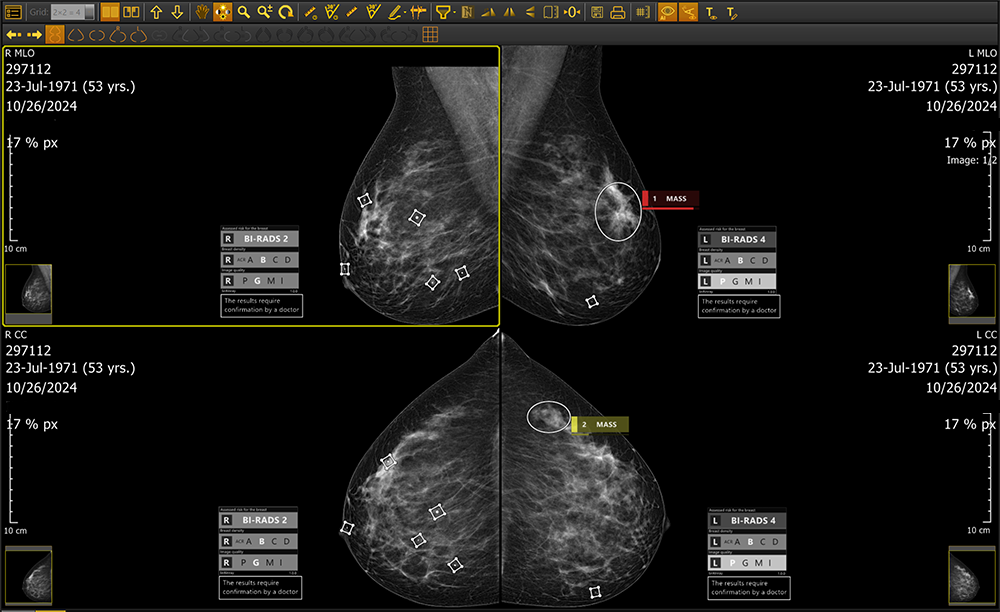

Whether deployed on-site or via the cloud, brAInray® seamlessly integrating with any PACS system, brAInray® analyzes full-field digital mammograms (FFDM) to detect and mark suspicious regions—highlighting calcifications, masses, asymmetries, and architectural distortions. It categorizes findings using ACR BI-RADS® standards and delivers automatic structured DICOM reports for clear, consistent clinical insights.